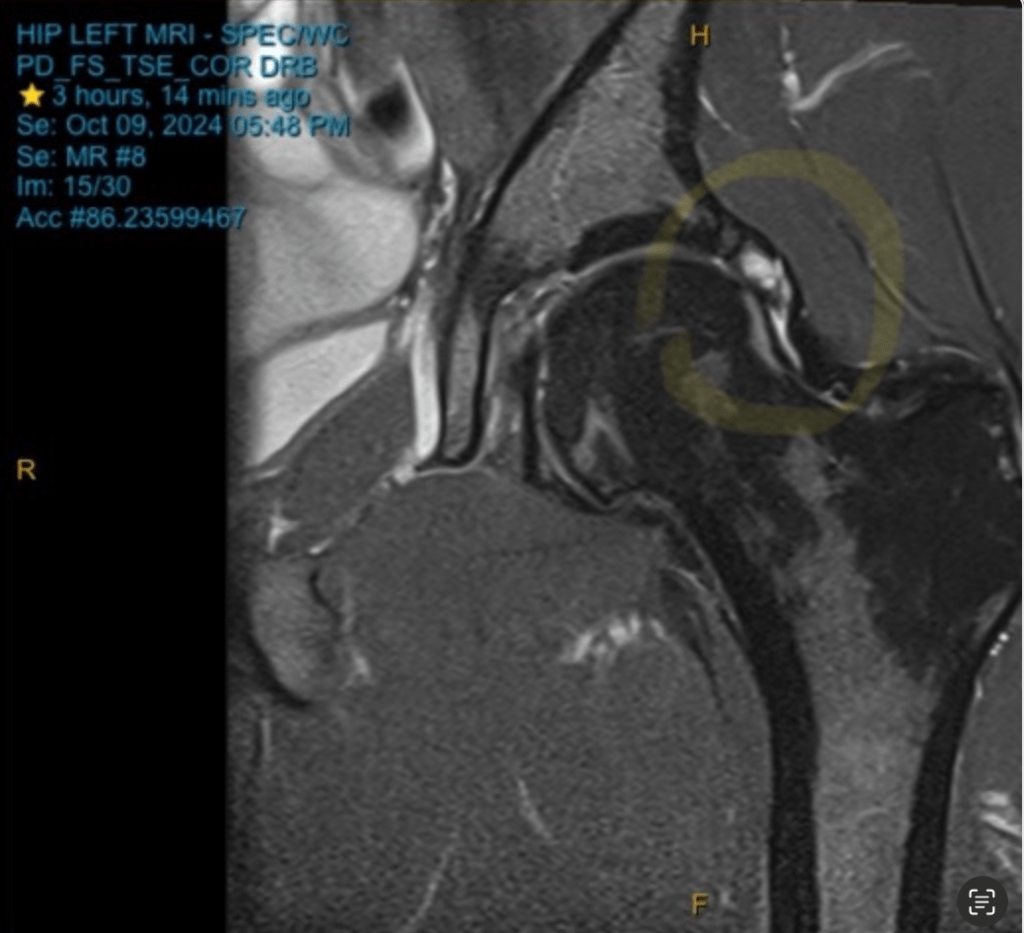

The strides weren’t the only exciting thing on Wednesday though. I had a MRI appointment to go and see what was actually occurring with my hip. I did feel a bit silly going in because it was starting to progress and be ok but I thought it would be a good idea none the less to actually see what was the issue. The whole MRI experience was actually pretty exciting. Get naked down to the undies, put a gown on, lie very still in a big tube of a machine, listen to it beep randomly, feel the camera pad heat up, no sense of time, just stay still. I almost fell asleep by the end. When it finished I asked the radiologist for a quick look at the pictures and noticed a few white spots but no real obvious stress fracture in my bone so I thought I was pretty right. Great success!

Not quite. Emma had a look at my results briefly that night and told me that I probably had a few thing going on in my joint but not necessarily with my bone. It wasn’t the worst case scenario but it wasn’t the best case scenario. Given how good my Tuesday run felt after doing some heavy lifting I opted to do some more heavy lifting work on Thursday before my run to yield the same benefits. It worked pretty well and this turned out to be one of the best runs I’ve had in the last month or so. Only 2/10 pain at worst, nice sunny day, cracked 70 minutes and felt like I had a rhythm going. The progression was continuing and it looked like I would be able to race on Sunday at this stage.

I still wanted to get a session done though beforehand just to see how my body felt at pace and how it would recover afterwards. On Friday I ran the RAO session, got myself sorted, and just before I was about to head out for a run Emma sent through my official results from the MRI. I had a labral tear and an intralabral cyst. Again, not great, but not too bad either. Means I can still run if I want too but I really need to take it careful and build up some strength in my left leg/hip to make sure it doesn’t get worse. The cyst and tear should repair themselves but if I overdo it then they won’t. Having to remove a cyst via surgery would be terrible.